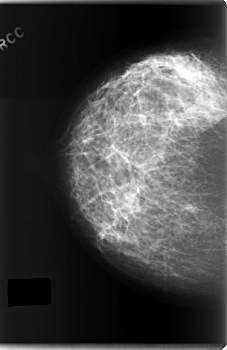

C_0203_1.RIGHT_CC

LEFT_CC LINES 6032 PIXELS_PER_LINE 3728 BITS_PER_PIXEL 12 RESOLUTION 50 OVERLAY

FILE: C_0203_1.LEFT_CC.OVERLAY

TOTAL_ABNORMALITIES 1

ABNORMALITY 1

LESION_TYPE CALCIFICATION TYPE PLEOMORPHIC DISTRIBUTION REGIONAL

ASSESSMENT 5

SUBTLETY 5

PATHOLOGY MALIGNANT

TOTAL_OUTLINES 1

BOUNDARY